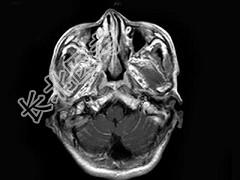

- 单项选择题男,55岁, 头痛40余天,呕吐2天伴共济失调。化验检查: 脑脊液蛋白:2006mg/l, 细胞数60个/mm3MRI平扫显示不佳,增强扫描后见脑膜强化及脑内小结节状强化以脑膜强化为明显, 据此最可能的诊断为 ( )